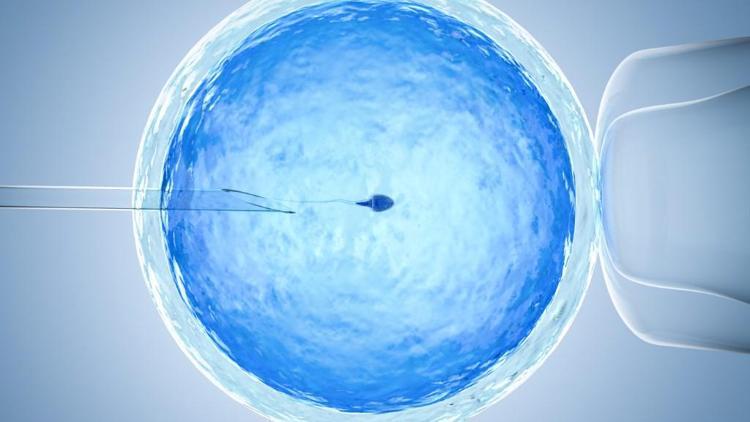

Dünyanın ilk tüp bebeği, 25 Temmuz 1978 yılında dünyaya gelmiştir.Çok hızlı bir gelişme kaydeden tüp bebek, infertilite tedavileri ve ilaçları günümüzde, tüm dünyada oldukça yoğun kullanılmaktadır.Özellikle tüp bebek tedavilerinde kullanılan ilaçlarda asıl amaç doğal olarak gelişen bir yumurtadan ziyade,daha fazla sayıda yumurta elde etmeye çalışmaktır.

Birden fazla yumurta elde etmeye çalışmaktaki amaç, döllenme ve bölünme evrelerinde problem yaşayan embriyoların elenmesi ve transfer etmeye değer iyi embryo elde etme şansını arttırmaktır.